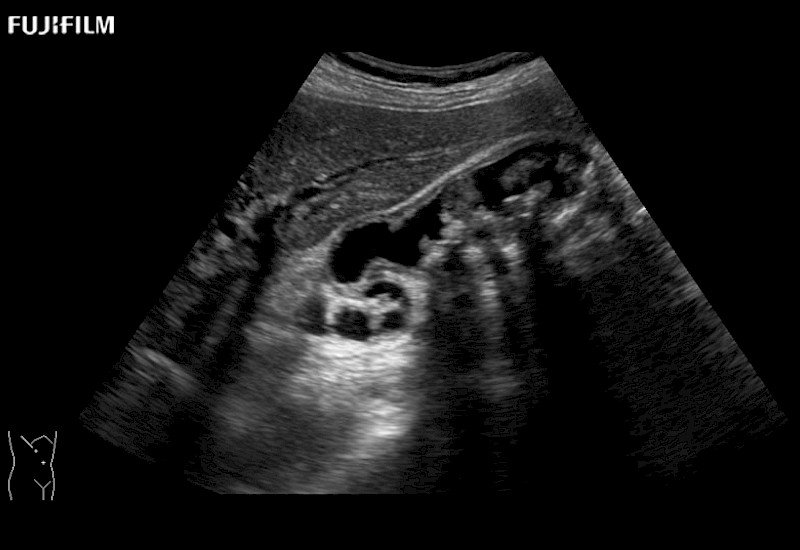

for use during general and laparoscopic procedures: Tumor localization & staging, Ablation, Resection, Biopsy, Transplant, Abdominal exploration, Robotic surgery

Our dedication to Laparoscopic Surgery allows us to offer superior image quality, outstanding system reliability and intuitive use of cutting edge technology.